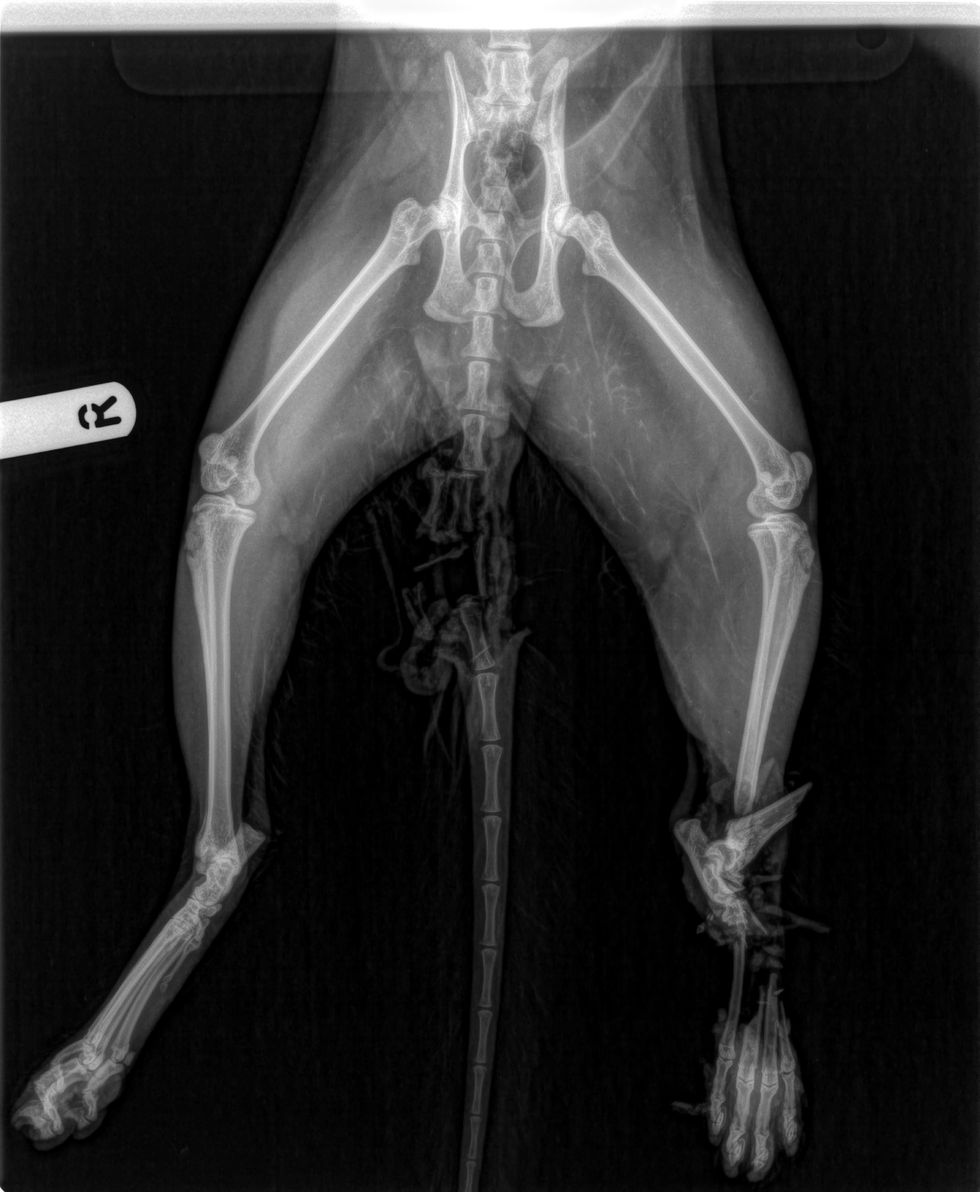

Hector needed his tail and most of a rear leg amputated after suffering injuries a vet said were the worst he had ever seen.

Vet Paul Smith said: “I’ve never seen a cat make it home with such awful injuries. His back end had almost been cut off by the train, and he’s so lucky to survive both that and the operation.

“The only two options were either to amputate or sadly put Hector to sleep.

“We wouldn’t normally have operated on both the tail and leg at the same time, but we had to act immediately to save Hector.”